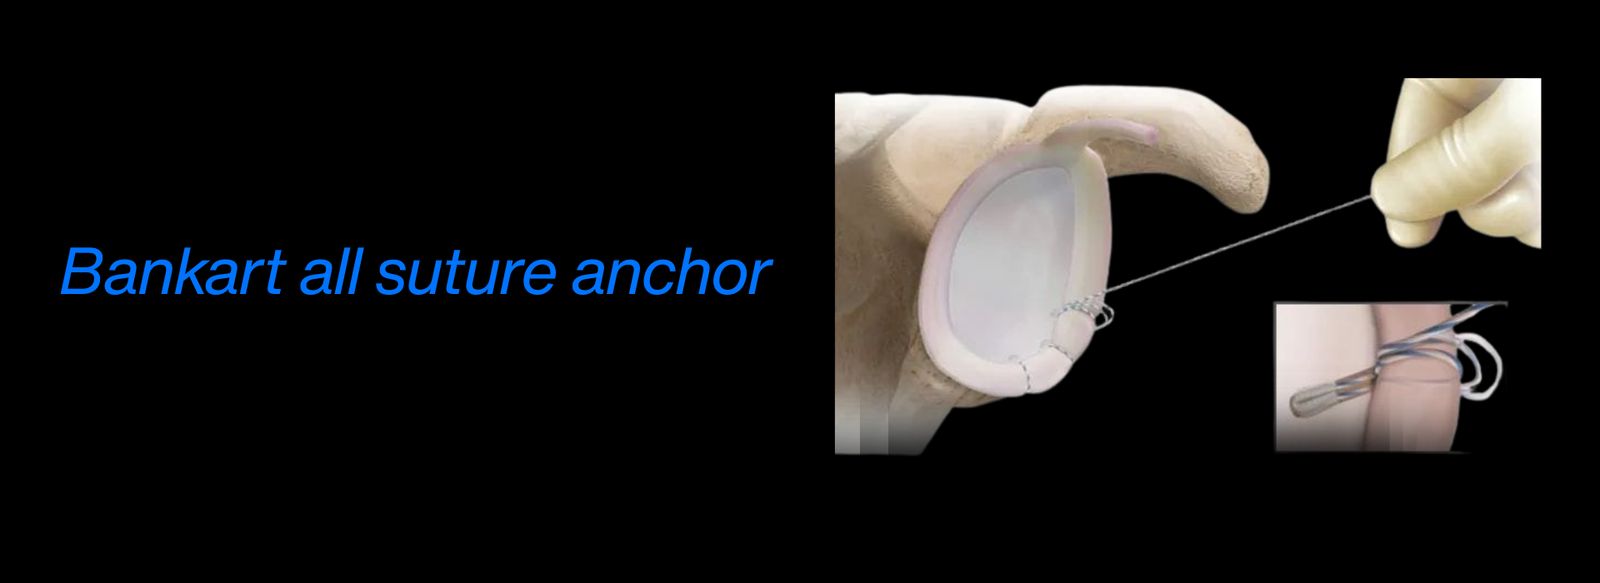

Fellowship in Arthroscopy: Expertise in minimally invasive surgery to diagnose and treat joint conditions, such as torn cartilage or ligament injuries, particularly of the knee, shoulder, and hip.